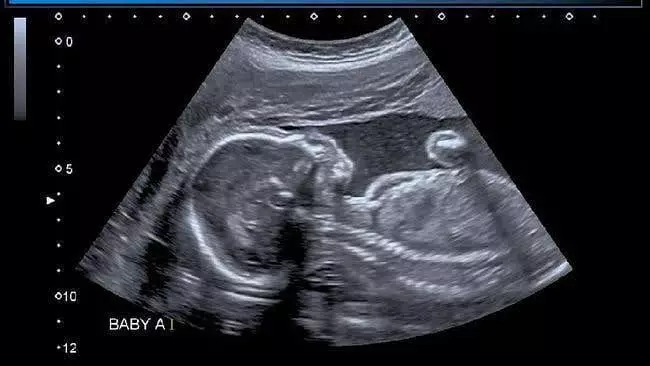

Brilio.net - Nadya Mustika Rahayu diketahui sedang hamil anak pertamanya. Seperti kebanyakan wanita yang sedang hamil, Nadya melakukan USG calon buah hatinya itu.

foto: Instagram/@nadyamustikarahayu

Di kolom komentar, banyak sekali warganet yang menulis pesan semangat untuk Nadya. Ada pula yang berkomentar kalau wajah sang janin tampak lucu menggemaskan.